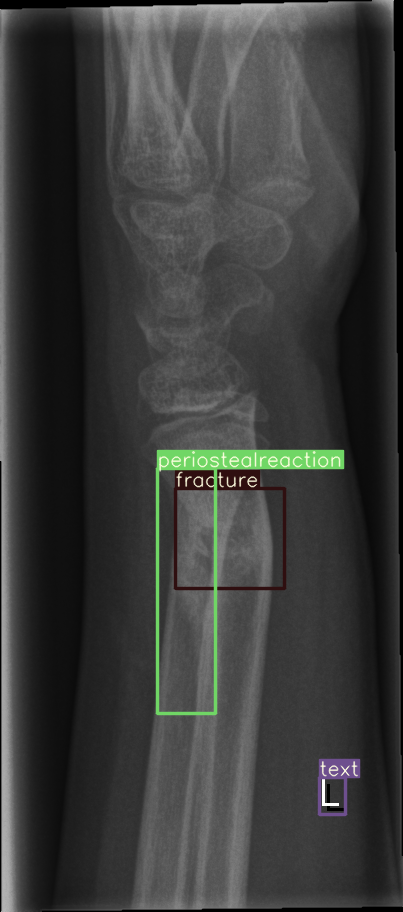

For our experiments, we selected the GRAZPEDWRI-DX images with bounding box annotations in YOLO format, which contains nine classes. Following the data division and augmentation approach outlined by [10], the dataset was randomly divided into 70%70\% training (14,23414,234 images), 20%20\% validation (4,0654,065 images), and 10%10\% testing (2,0282,028 images) sets. To further augment the training data, the number of images in the training set was doubled by adjusting the contrast and luminance of the images. The label distribution and bounding box statistics are shown in Figure 3. Examples of two training images with bounding box annotations from the GRAZPEDWRI-DX dataset are shown in Figure 4.

Refer to caption

Figure 4: Bounding box-annotated X-ray images of pediatric wrist trauma from the GRAZPEDWRI-DX dataset [8].